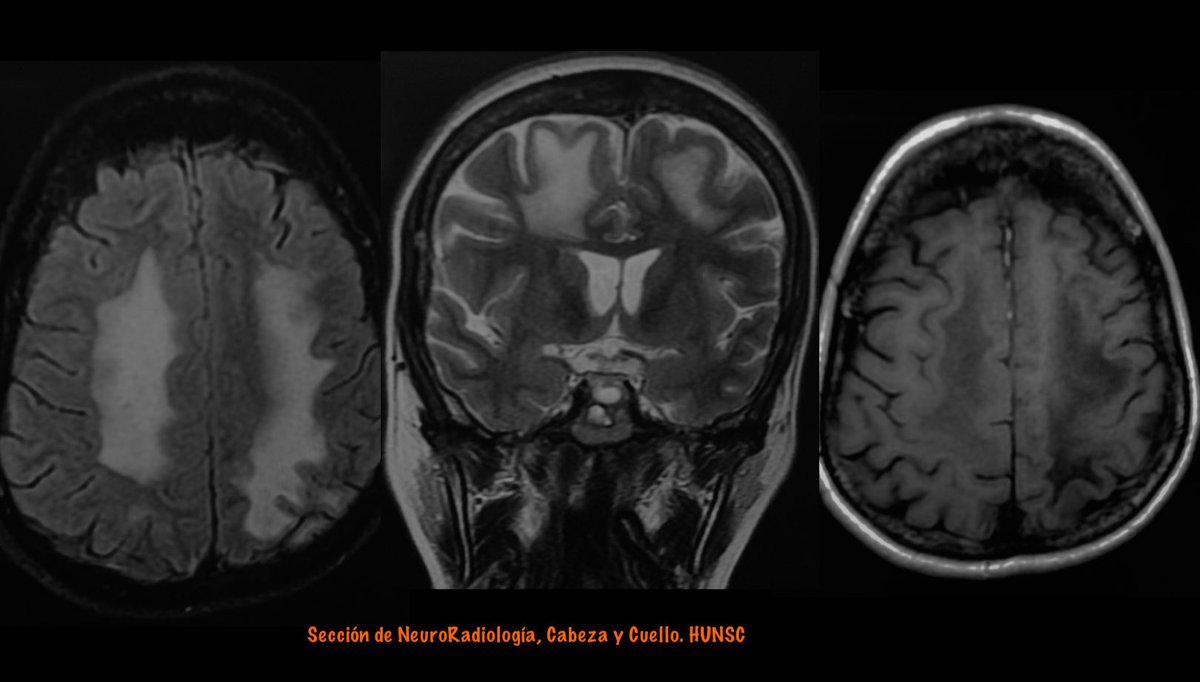

One patient/two sides……and two pathologies.

From left to right axial FLAIR, coronal T2 and axial T1 MRI Image

Right side:

Parasagital meningioma with vasogenic edema

From left to right: coronal T2, enhanced T1 and DWI. Image

Left side :

Progressive Multifocal Leukoencephalopathy (PML)

From Left: FLAIR, DWI and enhanced T1 MRI Image